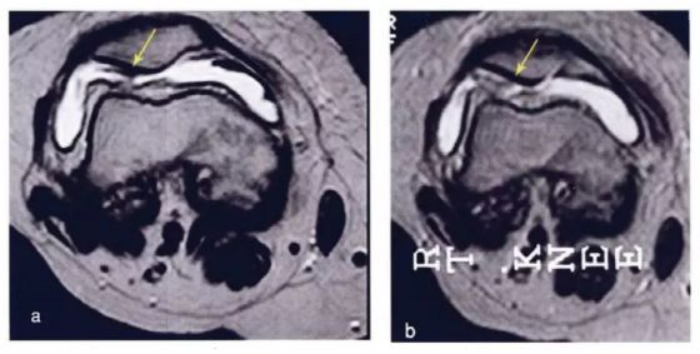

·研究结果:关节内注射骨髓间充质干细胞6个月后,,疼痛、、、、功能状态和步行距离均提高。。6名治疗组中3名患者在治疗前后的MRI比较可以看出,,该治疗对于改善软骨厚度,,,,修复组织延伸超过软骨下骨,,以及减少软骨下骨的水肿是非常显著的。。

下图a示意治疗前软骨,,,,b为治疗后6个月软骨,,,箭头所示为软骨修复位置。。